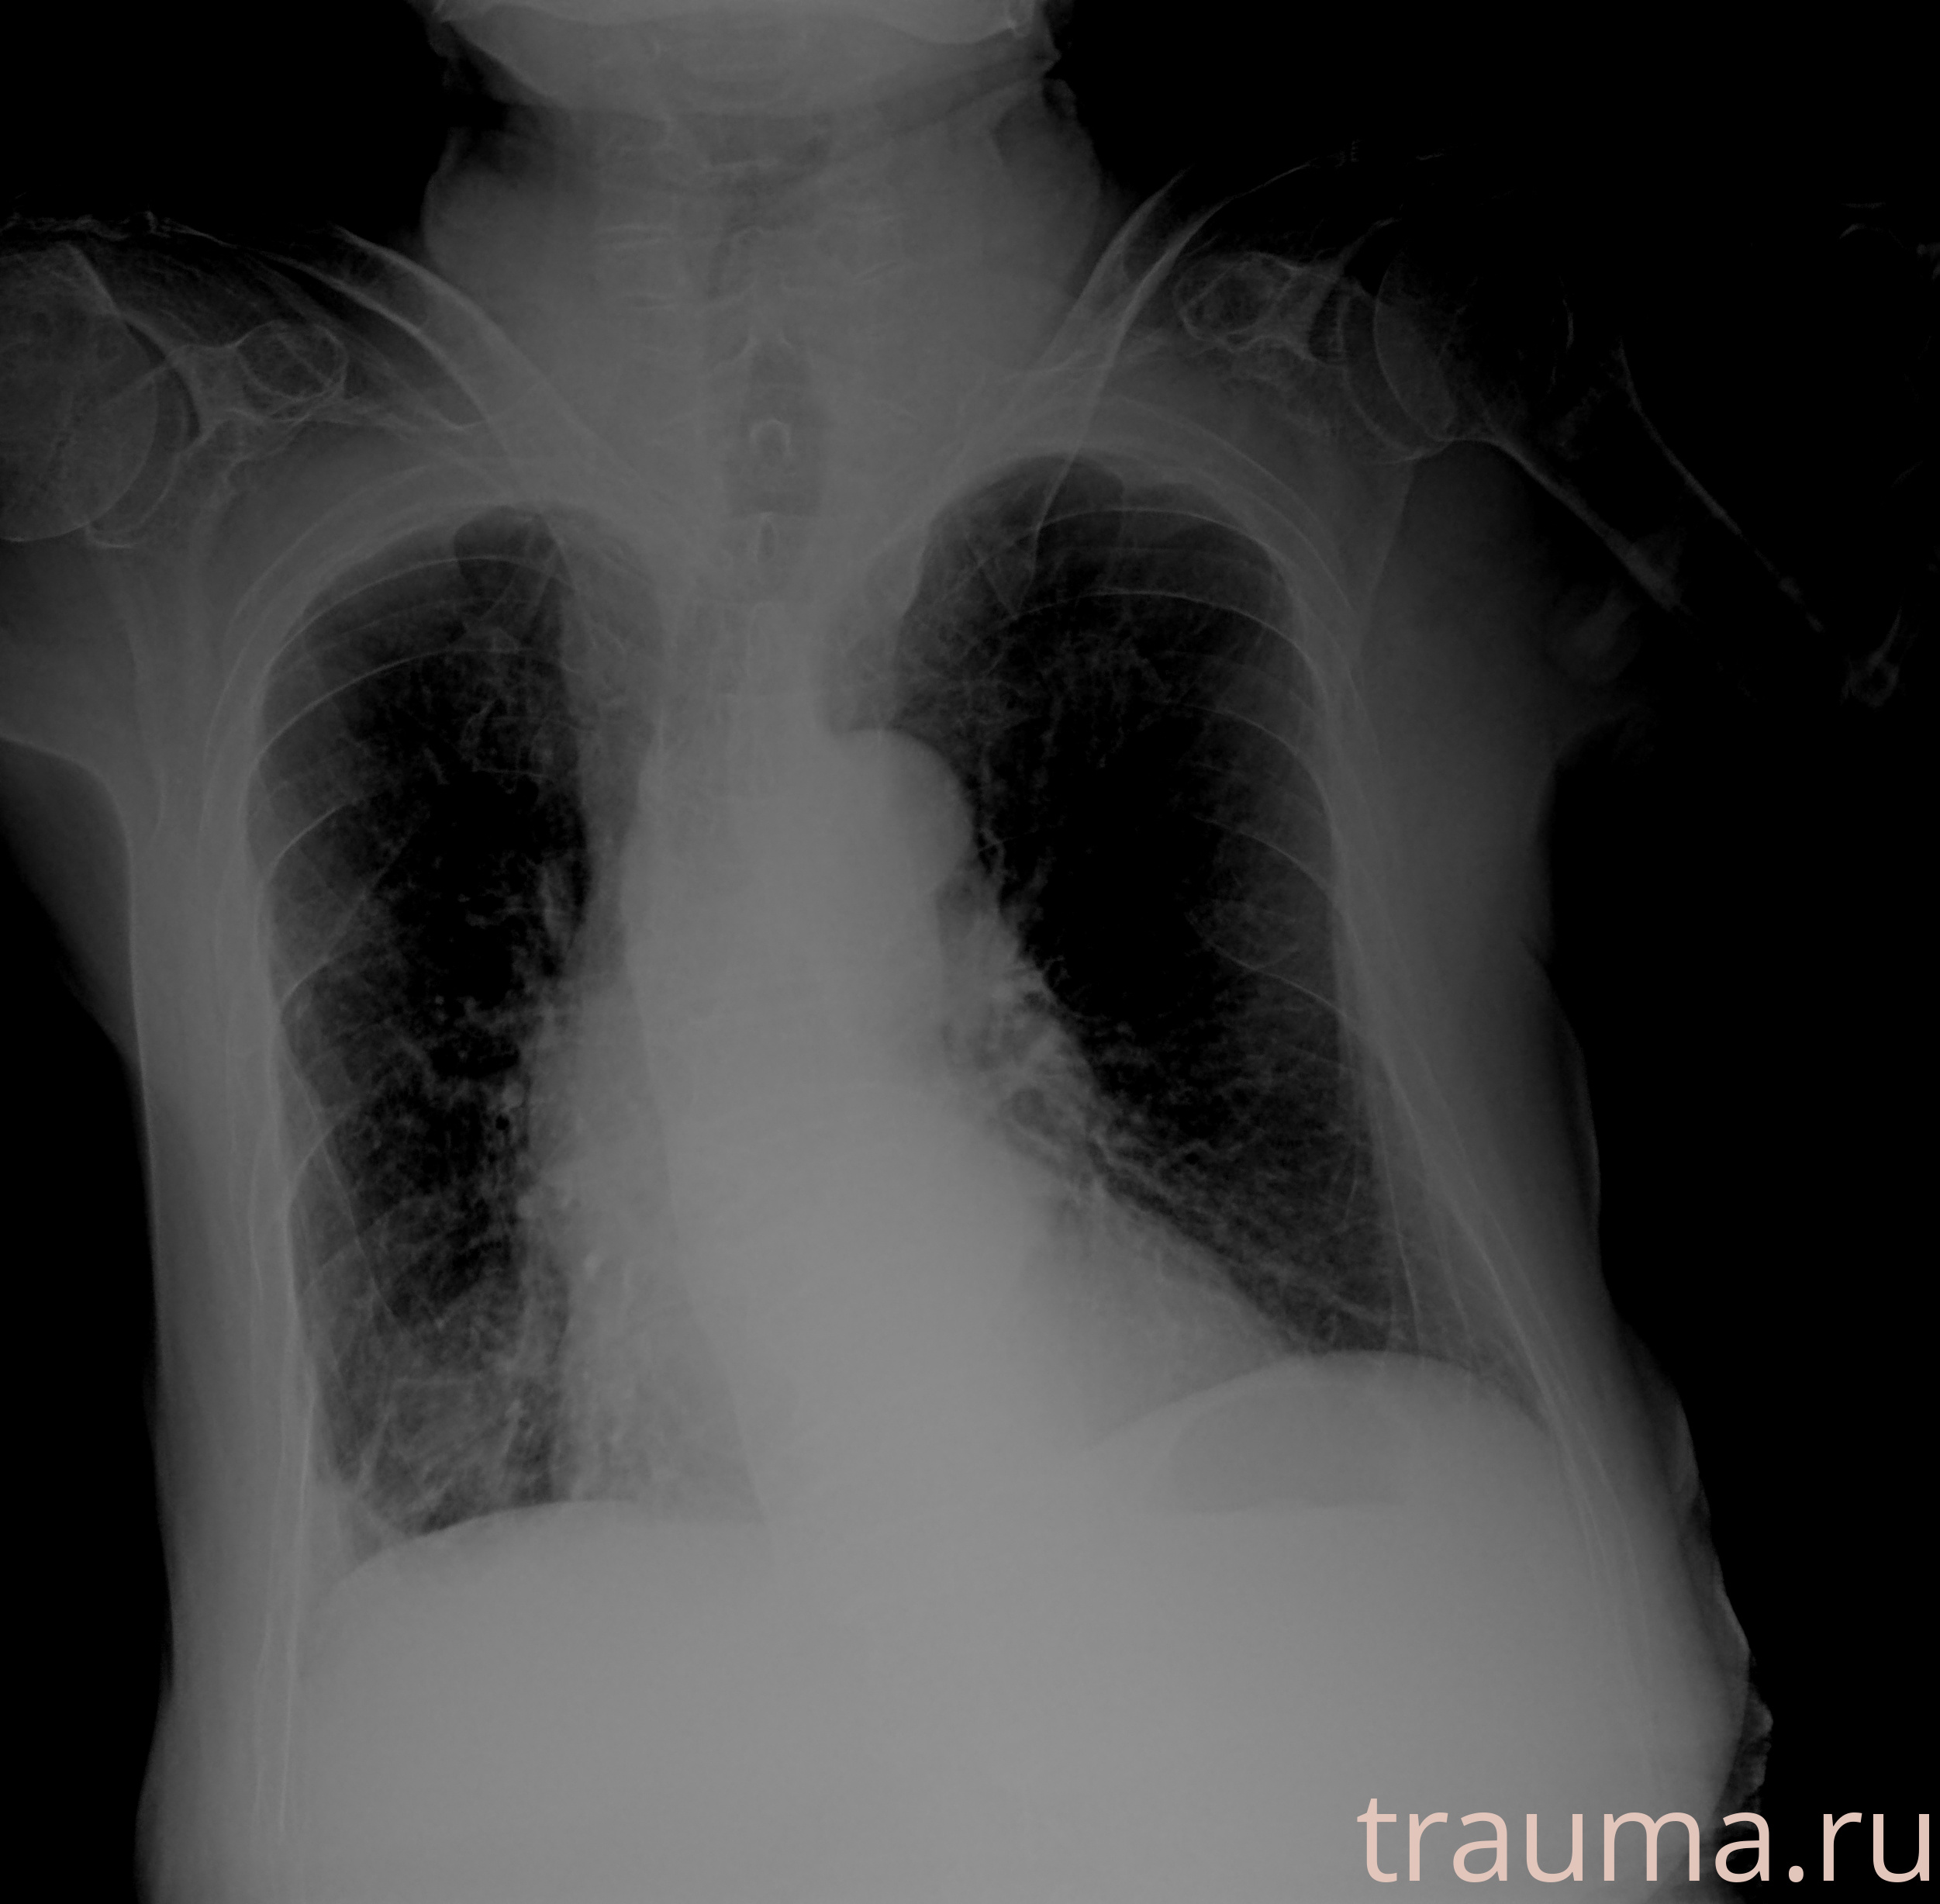

Рентгенограммы

Рентген на дому: по вашему адресу приезжает врач-рентгенолог, травматолог-ортопед с мобильным рентгеновским аппаратом, проводит диагностику травмы или заболевания, делает необходимые рентгенограммы, дает рекомендации по дальнейшему лечению. Получить качественные снимки в домашних условиях возможно благодаря уникальной методике, разработанной МосРентген Центром для института  Склифосовского

при переломе шейки бедра и пневмонии от компании МосРентген Центр - партнера Института имени Склифосовского